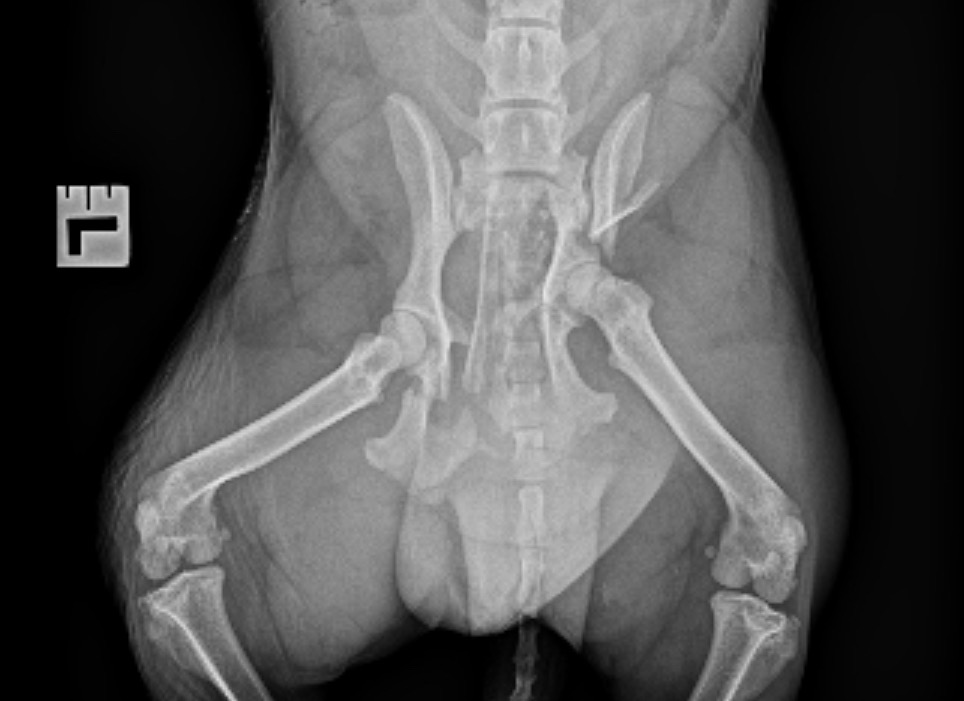

After advanced imaging and specialist assessment, we’ve discovered that Jack has severe pelvic and spinal injuries. Without major surgery, he’ll never regain the ability to walk comfortably or live a pain-free life.

• Orthopaedic and spinal surgery to repair multiple fractures